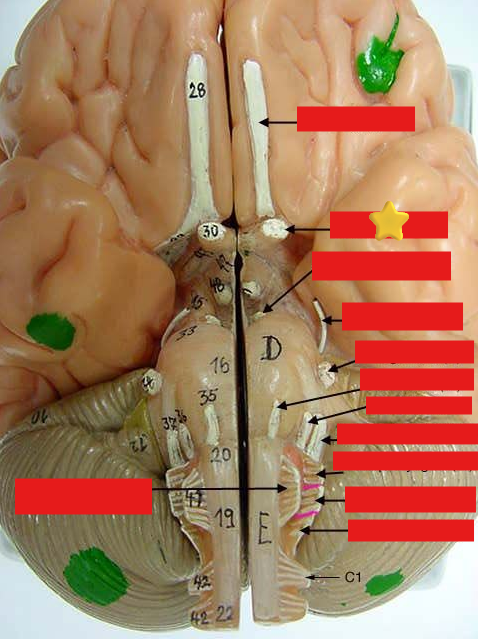

cranial nerves

12 Terms

1

olfactory

2

optic

3

oculomotor

4

trochlear

5

trigeminal

6

abucens

7

facial

8

vestibulocochlear

9

glossopharyngeal

10

vagus

11

accessory

12

hypoglossal